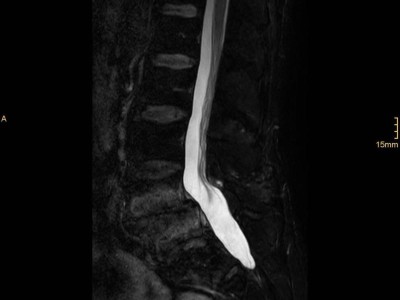

Wirbelsäulen-MRT bei Patient mit axialer Spondyloarthritis/© Springer Medizin, Arzt erläutert Modell der Wirbelsäule/© Matthias Stolt / stock.adobe.com, Wärmepflaster auf dem Nacken eines Mannes/© Nattawat Jindamaneesirikul / Getty Images / iStock (Symbolbild mit Fotomodell) (Symbolbild mit Fotomodell), ZFA TALKS - Nackenschmerzen/© (M) contrastwerkstatt / Stock.adobe.com (Symbolbild mit Fotomodell), Lendenwirbelsäule: Spondylolisthese mit aktivierter Osteochondrose (STIR Sequenz)/© Oikonomidis M et al. / all rights reserved Springer Medizin Verlag GmbH, Tabletten werden in Hand geschüttet/© O.Farion / Stock.adobe.com (Symbolbild mit Fotomodell), Psychotherapeutische Sitzung/© PeopleImages / Getty Images / iStock (Symbolbild mit Fotomodellen), Frau mit Hut im Wald/© (M) encierro / stock.adobe.com (Symbolbild mit Fotomodell), Raucher Zigarette Rauch /© buenaventura13 / stock.adobe.com (Symbolbild mit Fotomodell), Frau geht Spazieren/© HODEI / stock.adobe.com (Symbolbild mit Fotomodell), Abklärung von Rückenschmerz bei älterer Patientin/© andreswd / Getty Images / iStock (Symbolbild mit Fotomodellen), Erschöpfter Mann hält ein Glas Wasser/© Paolese / stock.adobe.com (Symbolbild mit Fotomodell), Ältere Frau mit Trainerin beim Sport/© jacoblund / Getty Images / iStock (Symbolbild mit Fotomodellen), Search Icon, Die Leitlinien für Ärztinnen und Ärzte, Facharzttraining Allgemeinmedizin, Ältere Person sortiert Medikamente/© Przemek Klos / stock.adobe.com (Symbolbild mit Fotomodell), Frau hat Bauchschmerzen nach dem Konsum von Brot/© weyo / stock.adobe.com (Symbolbild mit Fotomodell), Frau hält Tabletten-Blister und Beipackzettel in der Hand/© Vladimir Vladimirov / Getty Images / iStock (Symbolbild mit Fotomodell), Adipösem Jungen wird Blutdruck gemessen/© New Africa / stock.adobe.com (Symbolbild mit Fotomodell), EKG befunden mit System - EKG Essential/© Springer Medizin Verlag GmbH